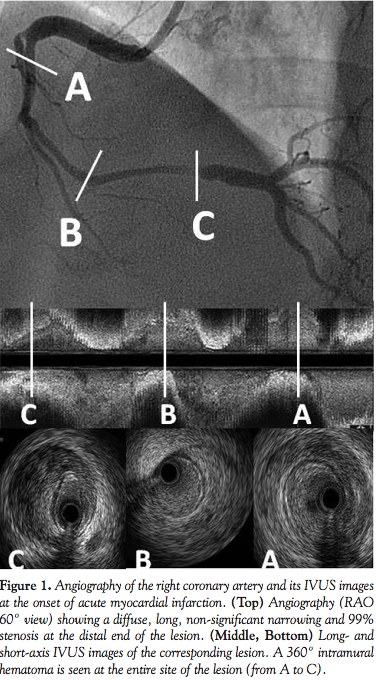

A 49-year-old male with light smoking history presented to our emergency department with sudden anterior chest pain. An electrocardiogram documented > 0.1mV ST-segment elevation in leads II, III, and aVF, suspected of being inferior acute myocardial infarction. Emergent coronary angiography (CAG) showed a long moderate stenosis originating from the proximal right coronary artery. At the distal end of the diffuse non-significant narrowing, a severe stenosis was located (Figure 1). Intravascular ultrasound (IVUS) demonstrated a long intramural hematoma which ranged from the proximal to the distal segment of the right coronary artery, concentrically compressing the true lumen (Figure 1). IVUS

identified no visualization of an intimal tear which suggested any entry point of coronary artery dissection.1 After intracoronary injection of isosorbide dinitrate, the severe stenosis regressed to moderate spontaneously. As no flow limit and no observation indicating ongoing ischemia were recognized, neither balloon angioplasty nor stenting were performed. His 9-day hospital stay was uneventful and without recurrent episodes of angina. We performed a follow-up coronary angiography at 30 days after the index procedure without any abnormal finding of the right coronary artery. IVUS delineated a complete restoration of the intramural hematoma (Figure 2). No inducible coronary spasm was observed by means of an intracoronary ergonovine maleate.